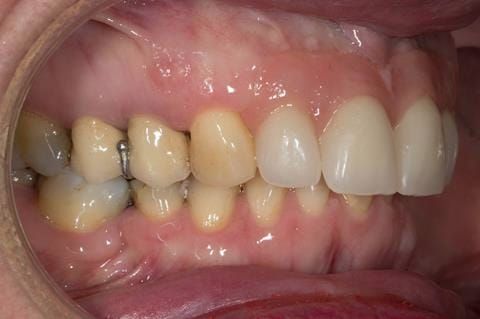

- High smile line showing gum above gingival zeniths of upper front teeth when smiling. Aesthetic failure of the upper four incisors with inflammation of the gingivae and mis-match of the gingival zenith levels.

- Other than the maxillary incisors the remaining dentition was in marginally better condition being moderately to heavily restored. Many will probably require replacement and restoration from time to time mainly from wear and tear owing to occlusal forces.

Following consultation and second discussion appointment the patient chose to have option 3 namely, a maxillary cobalt chromium based partial denture/protective occlusal splint. The clinical situation and treatment process is shown in detail below with photographs. The patient was successfully rehabilitated with this and her quality of life considerably improved. The clinical work was provided by Finlay and the technical work by Rowan.